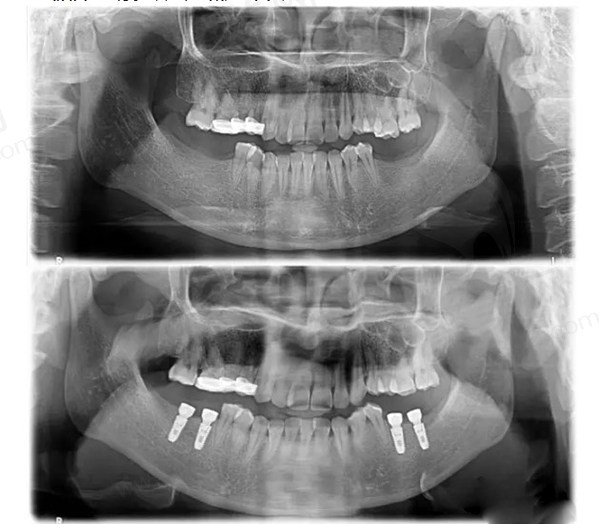

⊙长春传阳口腔种植牙怎么样?是3D导板种植技术吗?

1、是数字化3D导板种植技术

术前采用CBCT锥型束扫描和模型制作以及3D光学扫描制作三维种植模型,能帮助医生更准的确定植体植入的位置,优化种牙方案。

利用3D打印制作种植导板,医生在种植导板的辅助下便能高 效的把控整个种植过程,避开神经血管,提供种植牙手术的成功比率和舒适度,适用于所有类型的种植系统,以及复杂的多颗牙、全口半口牙齿种植。

4、疑难种植技术实力强

传阳口腔能开展穿颧穿翼种植手术,这项技术在国内各大口腔医院和机构里能开展的还是比较少的,可见传阳口腔的实力还是非常强的,怪不得很多疑难的全口半口种植牙都是会跑到它家来手术。